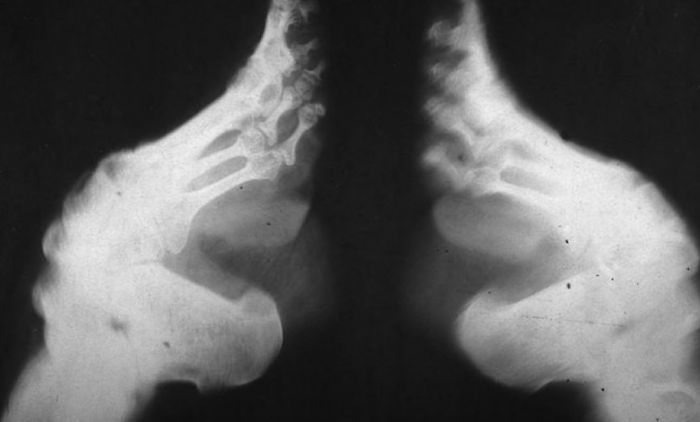

Везивање стопала, ради њиховог смањења је културна пракса, која је постојала у Кини од 10. века до успостављања Народне Републике Кине 1949. године, која је укључивала чврсто превијање стопала жена како би се променио њихов облик у естетске сврхе.

Везивање стопала обично би почињало када су девојчице имале између 4 и 6 година; неке су имале само 3 године, а неке чак 12 година. Мајке, баке или старије женске родбине прво су везивале девојчицама стопала. Крајњи циљ је био да стопала буду дугачка 7,5 цм, идеално стопало „златног лотоса“, иако је мало појединаца заиста постигло тај циљ. Четири мања прста су била увучена испод, повучена према пети и умотана завојима.

Сваки пут када су стопала одвезана, завоји и стопала су очишћени. Сва мртва кожа, пликови, осушена крв и гној су уклоњени. Процес је могао изазвати парализу, гангрену, улцерацију или смрт, иако је смрт била ретка. Везивање стопала наставило се до краја живота девојчице. Преко завоја су се носиле украсне ципеле и хеланке које су се могле разликовати у зависности од доба дана и прилике.